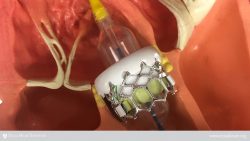

Transcatheter aortic valve implantation is a minimally invasive procedure to repair a damaged or diseased aortic valve. A catheter is inserted into an artery in the groin and threaded to the heart. A balloon at the end of the catheter, with a replacement valve folded around it, delivers the new valve to take the place of the old.

The tissue valve is made of bovine (cow) pericardium supported by a metal stent.

TAVI is performed while the heart is beating and does not usually require cardio-pulmonary bypass (use of a heart-lung machine). For the TAVI procedure, a catheter is placed in the femoral artery (in the groin), as is done for angioplasty. The catheter is guided into the heart. A compressed tissue heart valve is placed on the balloon catheter and positioned directly inside the diseased aortic valve. Once the new valve is in position, the balloon is inflated to secure the valve in place. The balloon is then deflated and the catheter withdrawn.

The procedure is performed with general anesthesia in a hybrid suite (which has both catheterization and surgical capabilities). A team of interventional cardiologists and imaging specialists, heart surgeons and cardiac anesthesiologists work together, using fluoroscopy and echocardiography to guide the valve to the site of implantation/replacement.